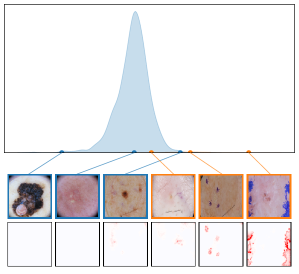

We further plot the distribution of CAV-based bias scores for biased and clean samples for the real-world artifacts ruler (ISIC2019) and pacemaker (CheXpert) in Fig. 8. We compute bias scores using the best performing CAV per artifact and use latent activations after the residual block of the ResNet50 model for ruler, and the convolutional layer of the VGG16 model for pacemaker. We show samples corresponding to the bias score in the top-1 and -99 percentiles of each set. Samples near the decision boundary are particularly interesting, as they may arise from labeling errors. Both examples demonstrate the retrieval of unlabeled artifact samples. The distributions of bias scores for additional artifacts are shown in Appendix A.6.2.